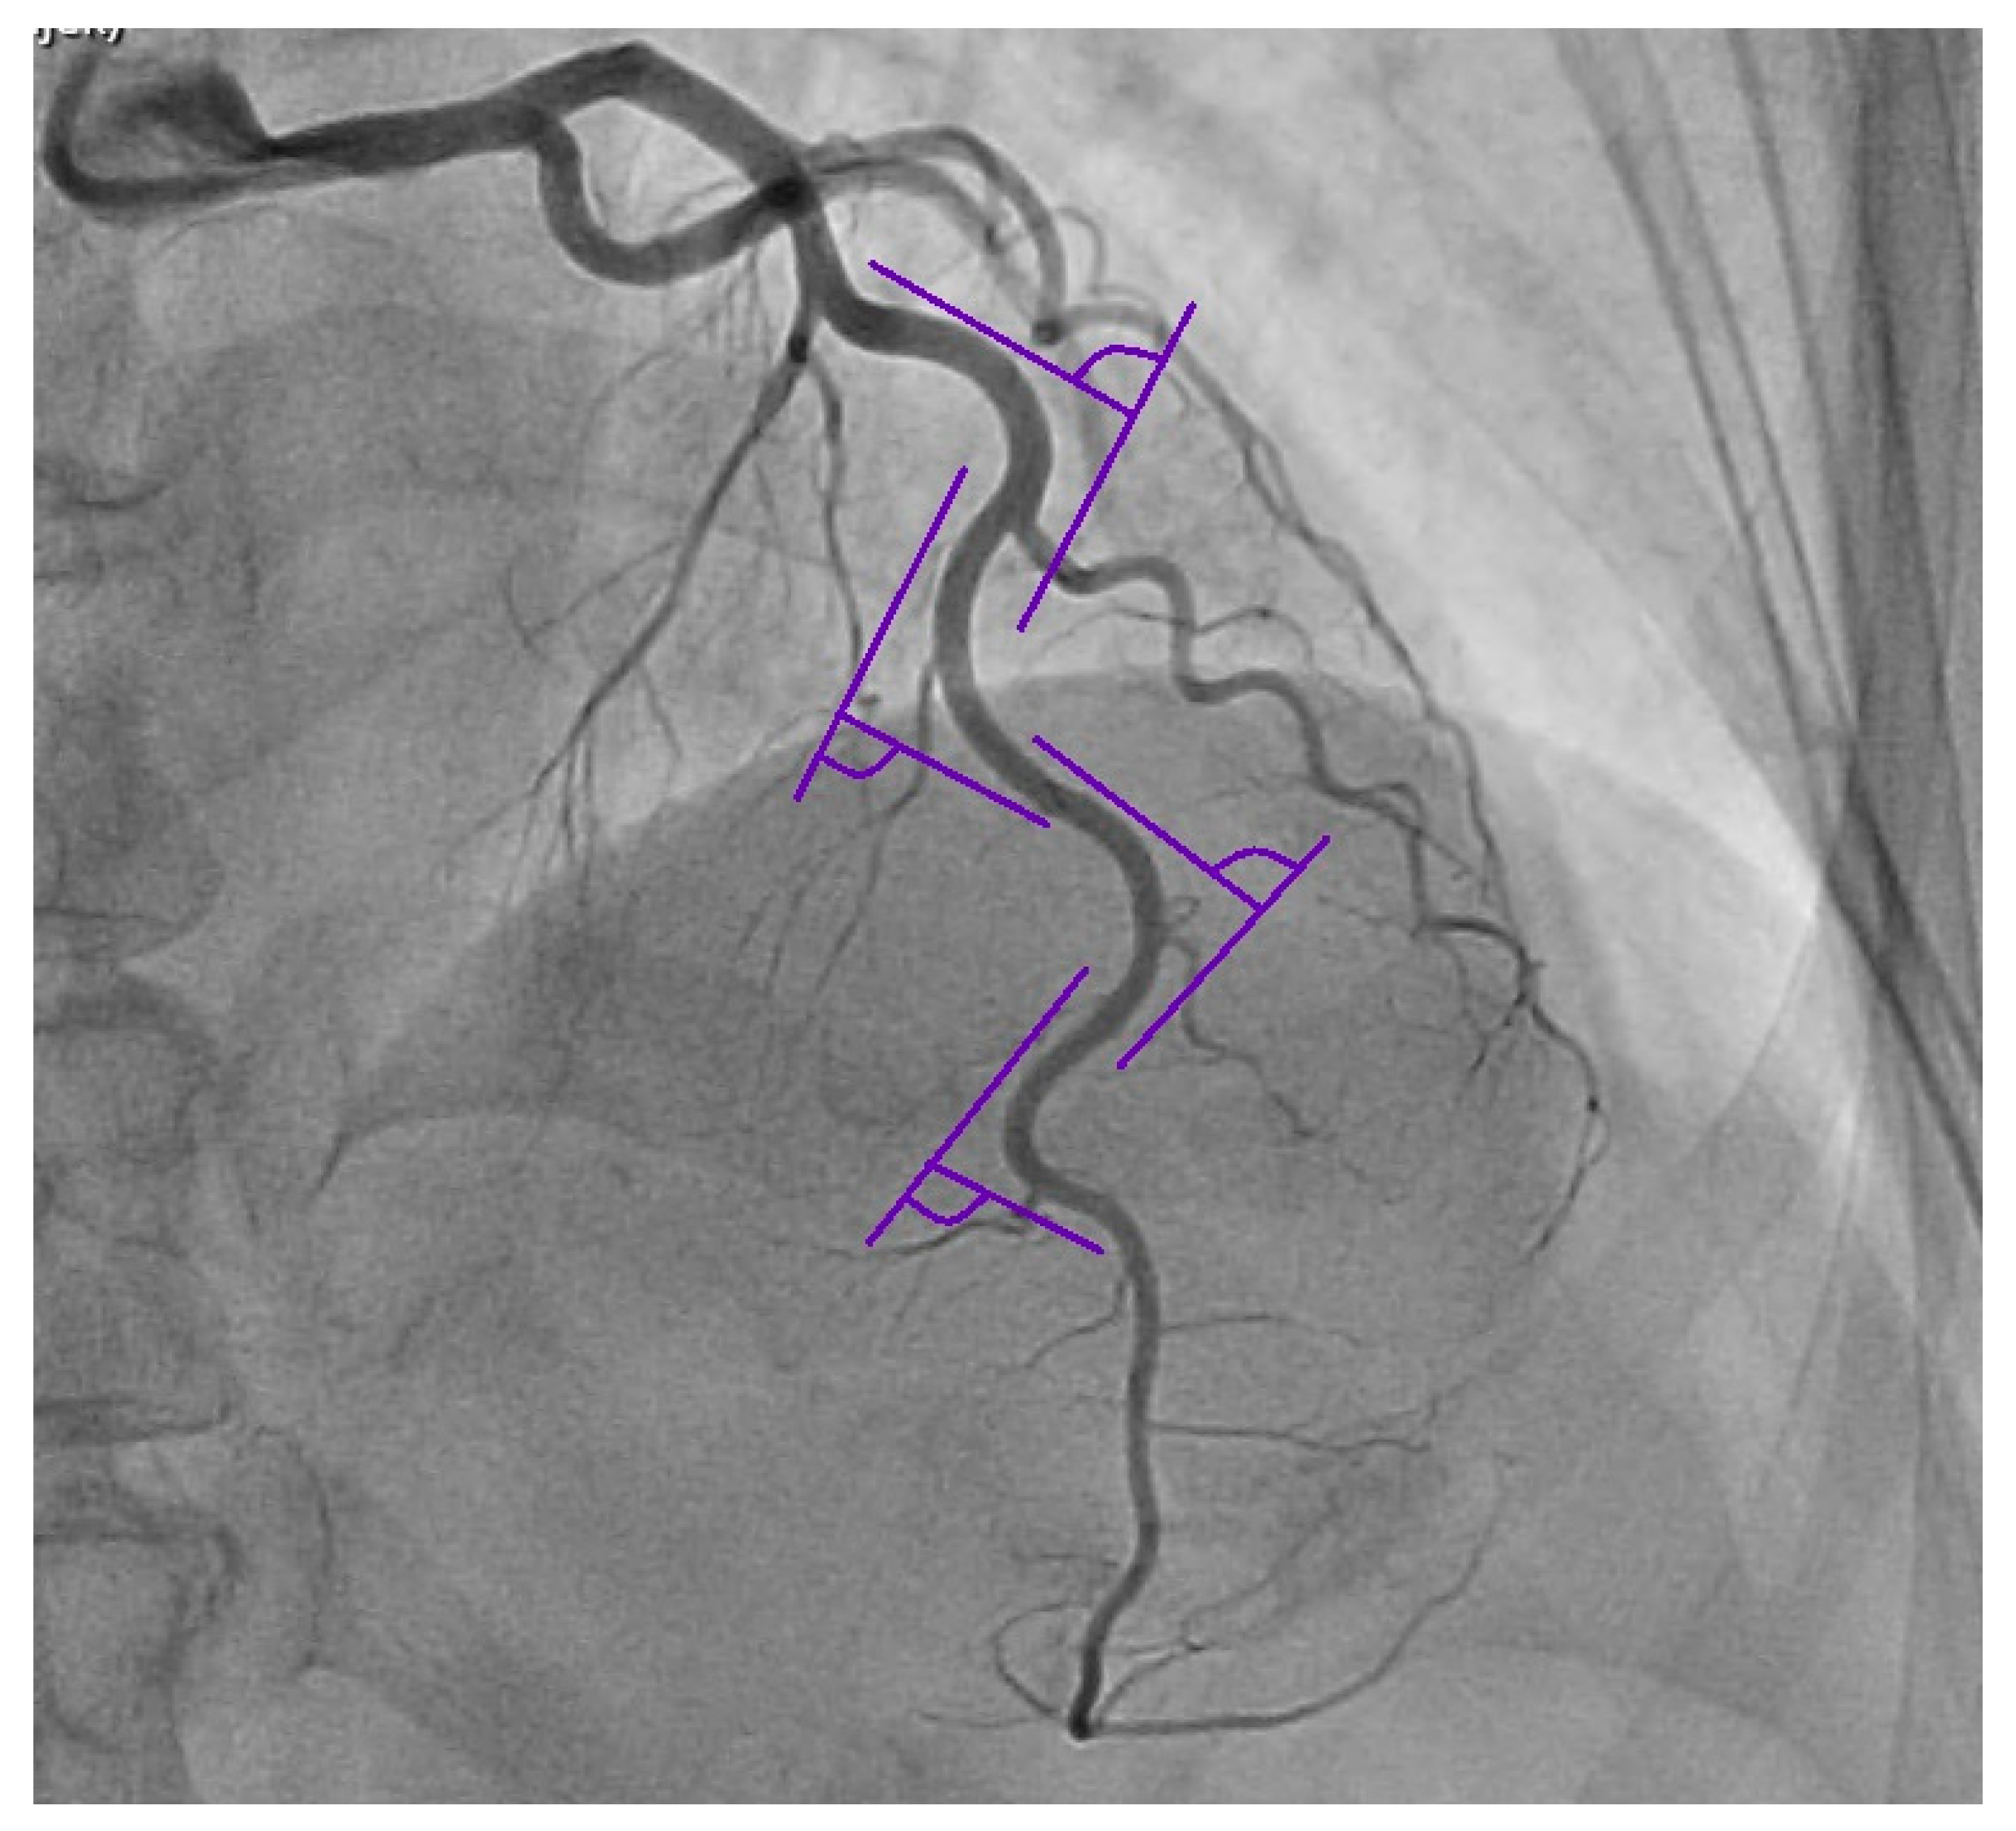

Angiographic analysis was performed in diastole and in systole from two-dimensional angiographic recordings. The left anterior descending coronary artery (LAD), the left circumflex coronary artery (LCX) and the right coronary artery (RCA) were observed by various angulations: RCA the 30-degree right anterior oblique view and the 30-degree left anterior oblique view; LAD the 30-degree right anterior oblique view with 60-degree cranial and the 30-degree left anterior oblique view with 60-degree cranial; LCX the 30-degree left anterior oblique view with 30 degrees of caudal angulation and at the 30-degree right anterior oblique view with 30 degrees of caudal angulation. The visually assessed luminal coronary obstructions of ≥50% in at least one main coronary artery were considered as CAD. We included patients with severe tortuosity, which was identified by the presence of ≥3 consecutive bends (presence of ≥45° change in vessel direction) along the main trunk (measured from their emergence in the aortic root or left main coronary artery to their ending, with exclusion of side branches) of at least one coronary artery (LAD, LCX, RCA) present in both systole and diastole [12], which is presented in Figure 1. An assessment of the coronary artery blood supply dominance was also performed. According to the arterial supply of the posterior descending artery (PDA) the patients were divided in three groups: (1) the right dominance group with PDA originating from the right coronary artery; (2) the left dominance group with PDA arising from the left circumflex artery; (3) balanced circulation group with PDA supplied from both the RCA and LCX [13].

Figure 1.

Representation of severe tortuosity of the coronary artery with bend angles measured according to our criteria.